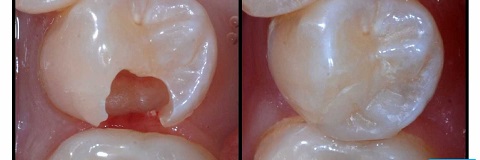

Trám răng thẩm mỹ laser (hoặc trám răng công nghệ halogen quang trùng hợp) là phương pháp trám răng hiện đại với việc sử dụng vật liệu trám là composite nha khoa kết hợp chiếu đèn laser (hoặc chiếu đèn halogen quang trung hợp) để khôi phục các phần răng bị gãy, mẻ, vỡ, lỗ sâu răng hoặc để khắc phục các khuyết điểm cho răng thưa hay răng hở kẽ.

Đầu tiên, nha sĩ sẽ đo màu răng thật để pha composite nha khoa sao cho có màu đồng nhất với răng thật, rồi đưa composite lên răng và dùng dụng cụ nha khoa để tạo hình cho răng sao cho giống răng thật với tính thẩm mỹ cao. Cuối cùng là chiếu laser để làm đông cứng composite và cố định vững chắc composite vào răng thật.

Trám răng thẩm mỹ laser – composite được áp dụng đặc biệt hiệu quả trong những trường hợp: Răng sâu, răng sâu nặng có lỗ sâu khá lớn, răng bị vỡ, răng gãy, răng mẻ, răng có kẽ hở (hở kẽ chân răng), răng thưa nhưng không quá nghiêm trọng.

– Composite được dùng ban đầu ở thể sệt nên dễ dàng tạo hình răng và không để lại khe hở giữa răng và chất liệu trám, sau đó bác sĩ sẽ chiếu đèn chiếu laser (hoặc đèn Hologen quang trùng hợp) để đông cứng composite và kết dính vào răng thật. Do đó, trám răng thẩm mỹ laser – Composite có tính thẩm mỹ cao, thời gian sử dụng lâu hơn.

– Chất liệu trám luôn có màu đồng nhất với răng thật (đo màu răng thật rồi mới pha màu composite) và khả năng kháng xuống màu, nhiễm màu giúp răng sau khi trám có màu như răng thật và giữ được màu lâu dài.

– Composite ban đầu là dạng sệt nên việc tạo hình răng sẽ dễ dàng do đó, về mặt hình thể răng cũng giống như răng thật.